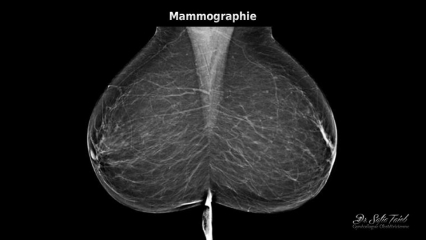

Qu’est ce que la mammographie?

La mammographie est une radiographie de chaque sein qui permet de détecter une éventuelle anomalie, elle s’effectue dans les 12 premiers jours du cycle menstruel.

Elle consiste à comprimer le sein puis l’exposer à une faible dose de rayons-X, cette compression permet l’étalement des tissus mammaires ce qui facilite la visualisation des structures du sein.

Cet examen comprend 2 clichés par sein et est réalisé en position debout, torse nu.

Pour visualiser le sein en totalité, il faut le comprimer entre deux plaques. Pour certaines femmes, la sensation de compression peut être inconfortable voire légèrement douloureuse mais reste brève.